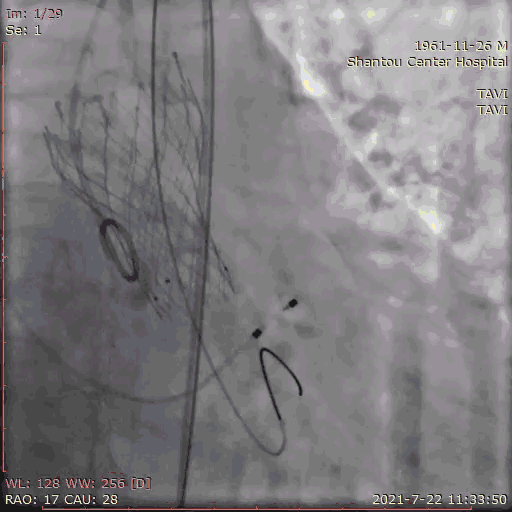

冠脉保护

指引导管将保护球囊送入左冠,防止紧急冠脉堵塞,若瓣膜释放后左冠灌注不良,则行开窗/烟囱植入冠脉支架。

送入输送系统

输送系统定位